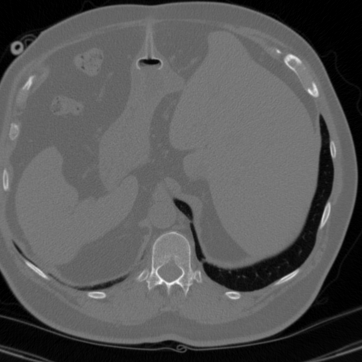

Figure 3 shows an example of a single frame of the reconstructed MR image sequences for an acceleration factor of using several approaches. We show the reconstructions that correspond to the single scalar parameter as well as to the scalar parameter pair (one spatial and one temporal) which are the parameters that maximize the PSNR of entire cine MR image and are obtained via a grid search by making use of the corresponding ground truth image. We also show the results that correspond to the parameters and which are respectively the single and the pair of scalar parameters that on average maximize the PSNR over the training set. These were obtained by treating the scalar regularization parameters as trainable parameters and training them by minimizing (33). We finally show the results for our estimated parameter-map with the proposed method. As observed, for all choices of the regularization parameters, the error with respect to the target image was significantly reduced compared to the initial zero-filled reconstruction. Further, we can see how the use of the estimated parameter-map yields the most accurate reconstruction and the best preservation of image details.

Figure 4 summarizes the results obtained over the test set with the help of box-plots. Compared to the initial zero-filled reconstruction, an improvement is clearly visible for all choices of the regularization parameter with respect to all reported measures and for all acceleration factors. In addition we see how allowing the temporal direction to be differently regularized than the two spatial dimensions positively influences the results compared to having one global parameter (orange vs blue). Last, we see how using the proposed method to estimate an entire spatio-temporal parameter-map further surpasses the scalar regularization parameter-maps (green vs orange and blue), especially in terms of SSIM. Table 1 lists the mean and the standard deviation of all TV-reconstructions. The results are consistent with the ones from the box-plots.

Figure 5 shows an example of a spatio-temporal regularization parameter-map which was estimated using the proposed approach for an acceleration factor of . The network estimates the regularization parameter-map to be pointwise relatively consistenly higher than the spatially required regularization. This result is in fact expected as the temporal dimension is the one for which the gradients of the images are the sparsest because of the high temporal correlation. Further, we see how the network consistently predicts both the spatial regularization as well as the temporal regularization to be less strong in the area where most of the movement is expected, i.e. in the cardiac region.